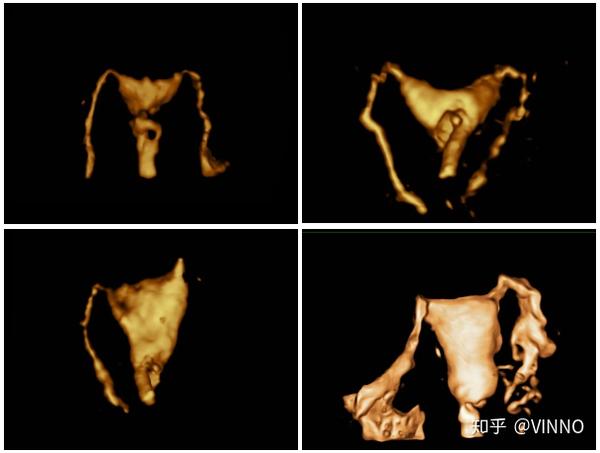

宫腔三维成像(宫腔下段子宫内膜息肉)经阴道四维子宫输卵管造影成像这